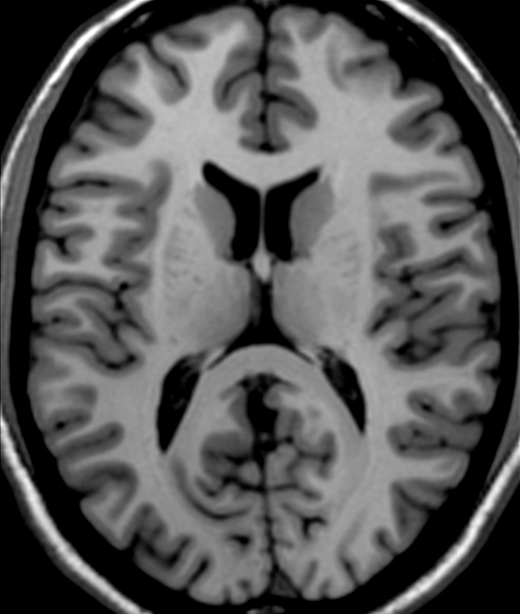

Identify the splenium of the corpus callosum